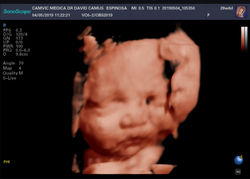

Ultrasonido de crecimiento fetal y bienestar fetal con flujometría

En el estudio de crecimiento fetal y bienestar fetal, lo realizamos después de la semana 30 del embarazo y en este estudio evaluamos el correcto crecimiento del bebe, así como el estado de bienestar del bebe, en busca de datos de sufrimiento fetal. Se evalúa la posición final de la placenta., así como la posición final del bebe. Evaluamos con herramientas avanzadas como el doppler los datos de la hemodinamia y flujometría materno fetal en búsqueda de marcadores de sufrimiento fetal.

Mediante el análisis a detalle de estos elementos nos permite evaluar la fecha y la forma más segura para él bebe y a la mama, para la finalización del embarazo, ya sea por parto normal o cesárea.